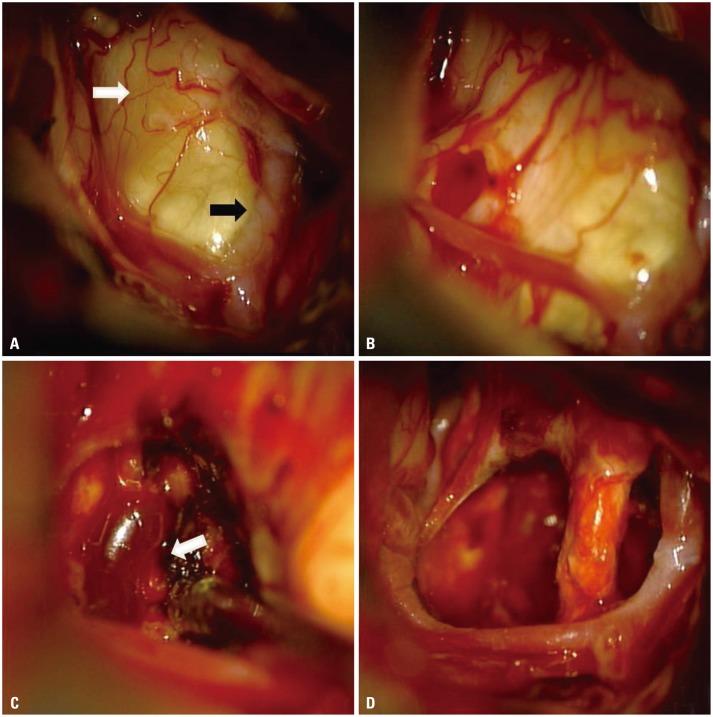

Hemangioblastoma (HBL) in the pituitary stalk is extremely rare. Only 16 such cases have been reported in the past and 5 cases have been treated with surgical procedure. Here, we report surgical case of HBL in the pituitary stalk diagnosed in a 34-year-old woman. The patient underwent a gross-total resection via the modified lateral supra-orbital approach. No recurrence was observed in two years after surgery. To our knowledge, this is the 17th case of HBL in the pituitary stalk and the 6th surgical case. If the tumor is symptomatic and the volume is over 5 cubic centimeters as in our case, we recommend that the surgical resection of the HBL in the pituitary stalk is a more safe and reasonable than radiotherapy.

垂体柄血管母细胞瘤(HBL)极为罕见。过去仅报道过16例此类病例,其中5例接受了手术治疗。在此,我们报告一例34岁女性被诊断为垂体柄HBL的手术病例。该患者通过改良眶上外侧入路进行了全切除。术后两年未观察到复发。据我们所知,这是第17例垂体柄HBL病例,也是第6例手术病例。如果肿瘤有症状且体积超过5立方厘米,如我们的病例所示,我们建议垂体柄HBL的手术切除比放射治疗更安全、更合理。